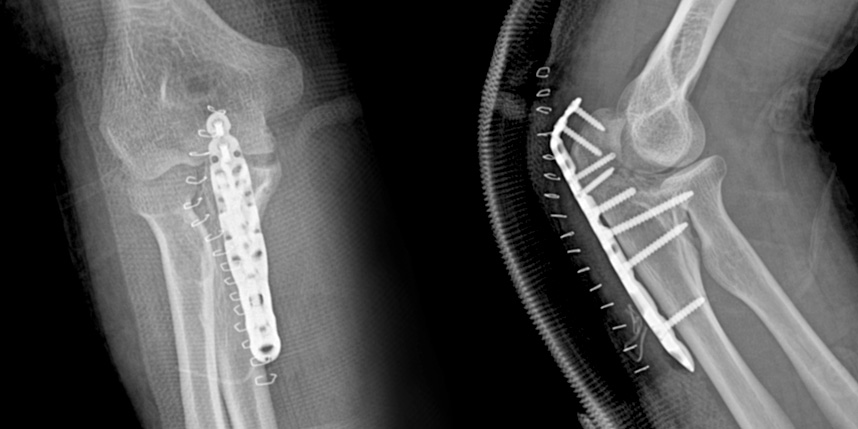

골절은 정확하게 골절편을 잘 맞추고 고정하는 것이 중요합니다. 특히 관절면을 잘 맞추는 것이 중요합니다.

무릎 골절

상완골 골절